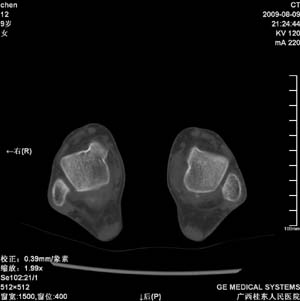

标题: PED2867:右侧内踝肿胀,骨质改变,请各位老师会诊 [打印本页]

标题: PED2867:右侧内踝肿胀,骨质改变,请各位老师会诊

九岁小朋友,近期左侧内踝疼痛,局部肿胀,平时无特殊,近期经常溜干冰

对不起,是右侧内踝肿胀

双踝关节骨质及发育未见异常。